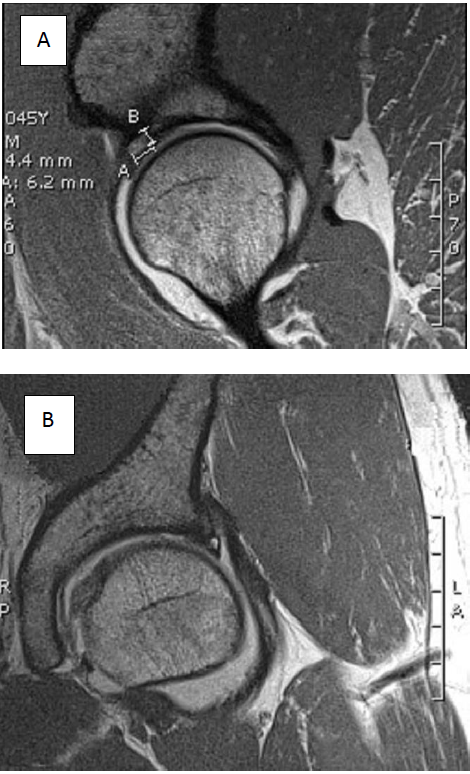

En la artroresonancia magnética se observó: en la cadera izquierda un fémur tipo CAM, con ruptura del labrum anterosuperior y quiste intralabral. Lesión condral superior, con pequeños pits en transición cabeza-cuello (ver Figura 1 y Figura 2).

RMN: permite identificar el estado del cartílago articular y del labrum. La artrografía por RMN es el examen de elección porque delinea mejor los fragmentos del labrum y sutiles lesiones del cartílago, ya que el medio de contraste intraarticular distiende las partes de la articulación y permite una mejor visualización de sus estructuras10, 18. Este método fue el utilizado para confirmar el diagnóstico del paciente al evidenciar el daño articular.

La medición del ángulo α puede aproximar al diagnóstico de SPFA tipo CAM. Esta medición consiste en dibujar un círculo que pase por los bordes laterales de la cabeza femoral, luego, se traza una línea oblicua a través del centro del cuello femoral que biseque el círculo previamente dibujado. Finalmente se traza una segunda línea desde el centro del círculo hacia el punto en el que la cabeza femoral o el cuello protruye más allá de los confines del círculo. El ángulo α es el que se forma entre estas dos líneas y un valor mayor a 50° es anormal. Es importante resaltar que este ángulo puede estar aumentado en numerosas patologías que afectan la anatomía normal de la cabeza y del cuello del fémur, no es específico de SPFA. Es así como la presencia de estas tres características sugiere un SPFA tipo CAM: ángulo α mayor a 55°, lesión anterosuperior en el cartílago acetabular y erosión en la región anterosuperior del labrum; según observó Kassarjian, en varios de sus estudios21.